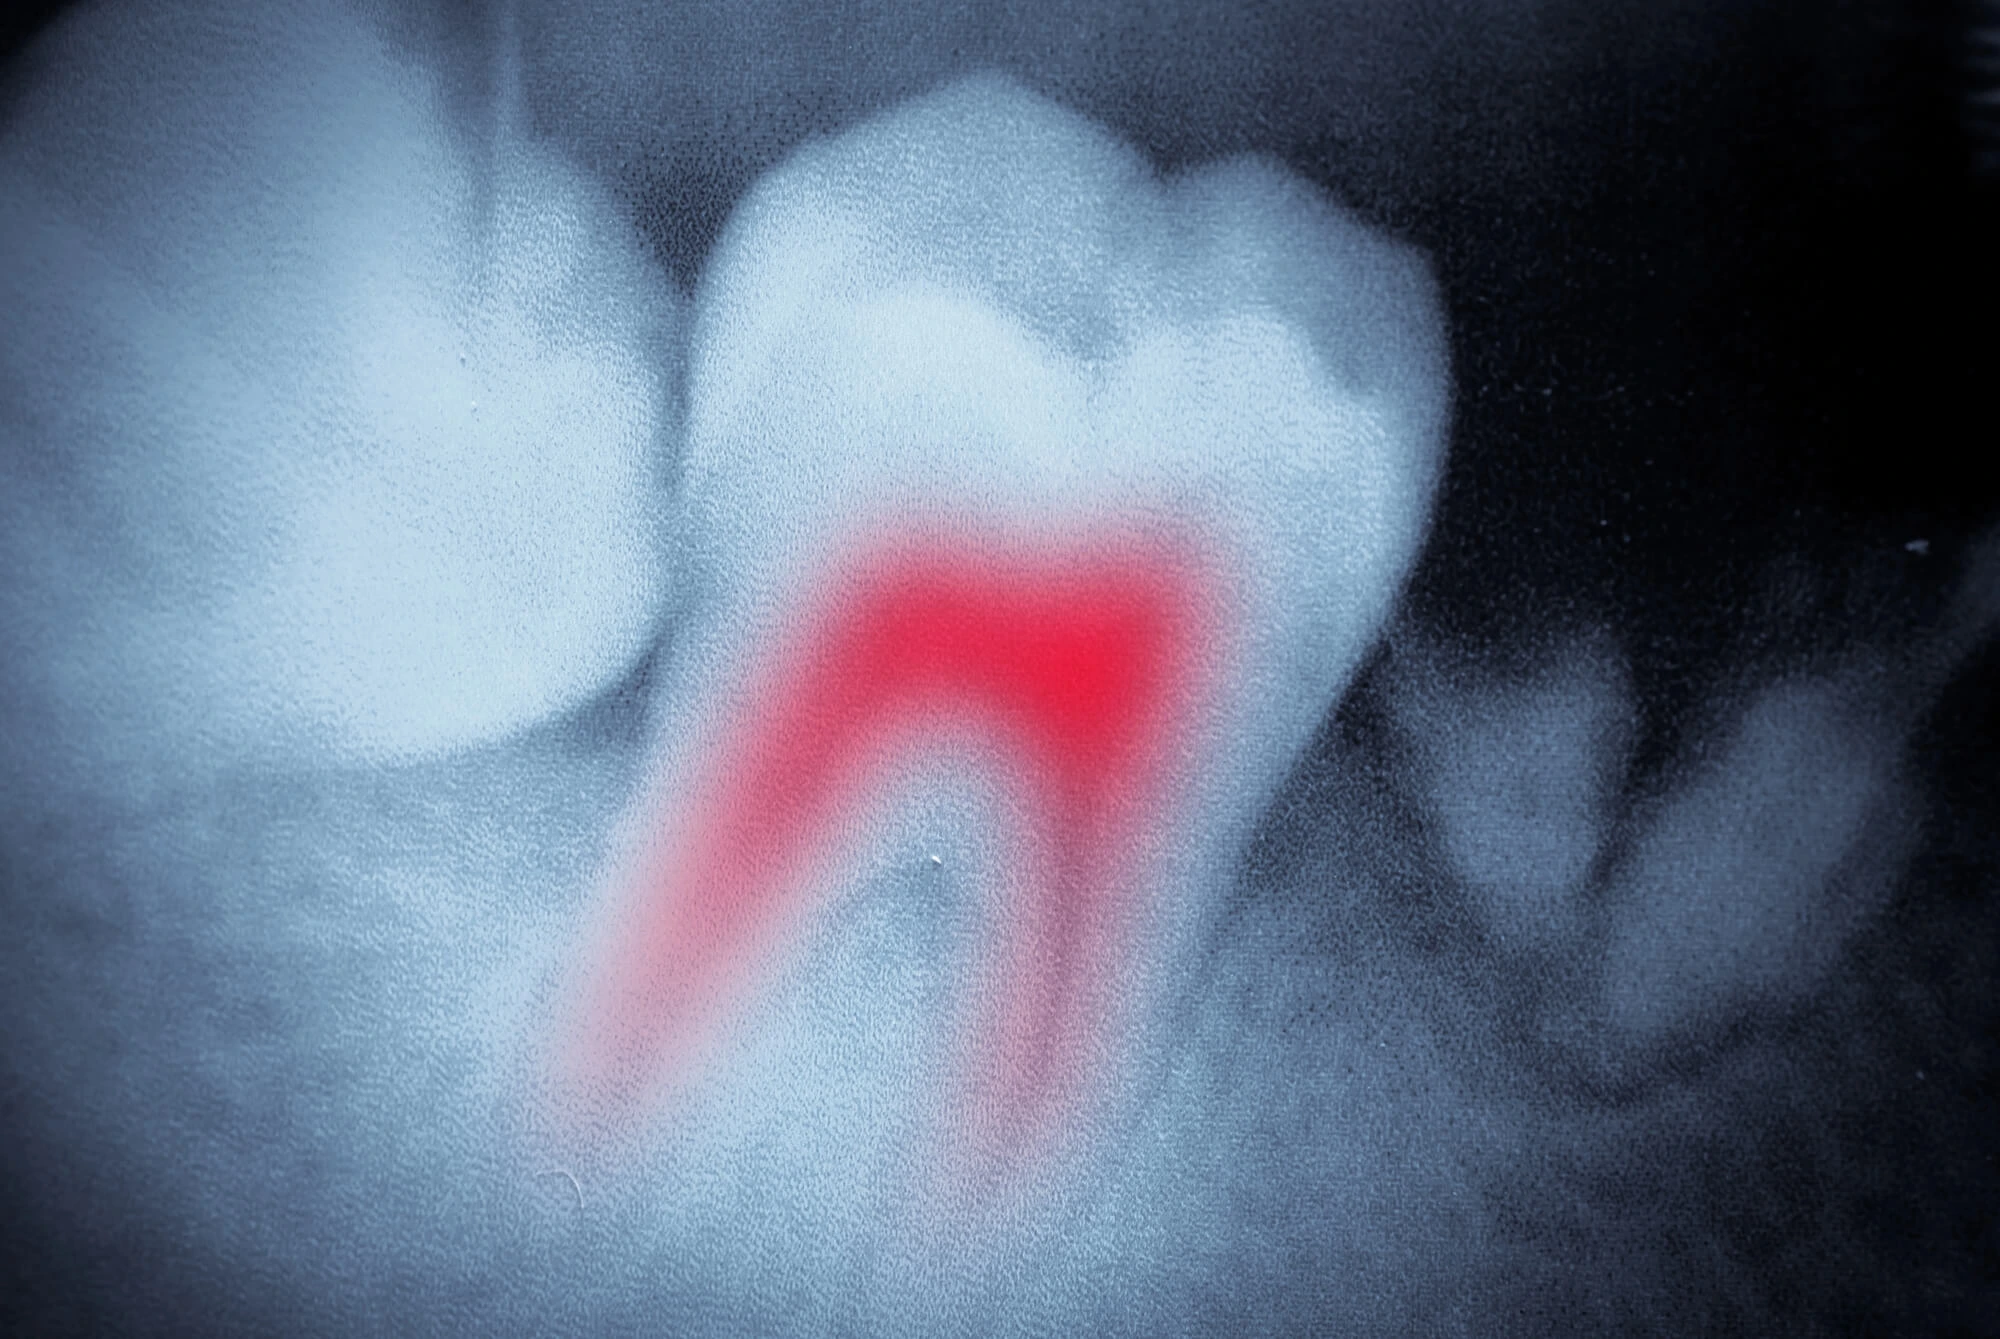

Not always. Sometimes, the nerve inside your tooth dies quietly. You might not feel pain, but that doesn’t mean everything’s fine. Your dentist may notice signs of infection or deep decay during a routine exam or X-ray. Catching these issues early makes treatment easier and prevents future problems. That’s why keeping up with regular dental visits matters.